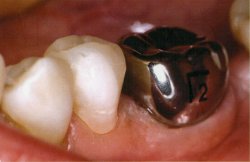

Dental Crowns